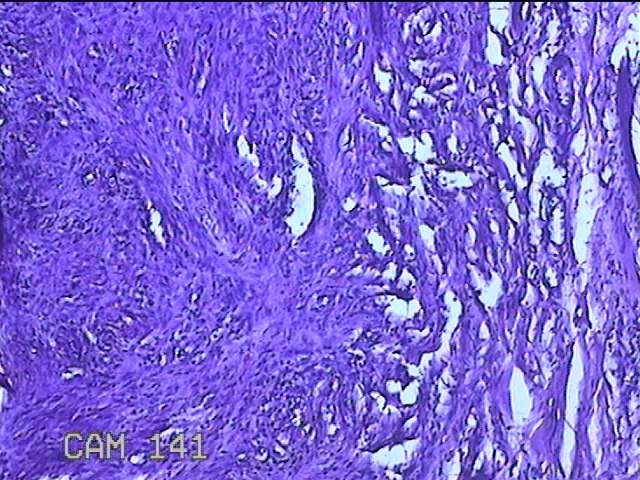

左侧臀部结节

性别

男

年龄

40岁

临床诊断

皮下结节

一般病史

发现左侧臀部结节1年余。

标本名称

大体所见

灰白粉红色组织1.3x0.8x0.3cm一块,表面带梭形皮肤1.3x0.8cm,皮下见结节1.3x1x0.7cm一个,切开结节呈实性,切面灰白粉红色,质软。

图4